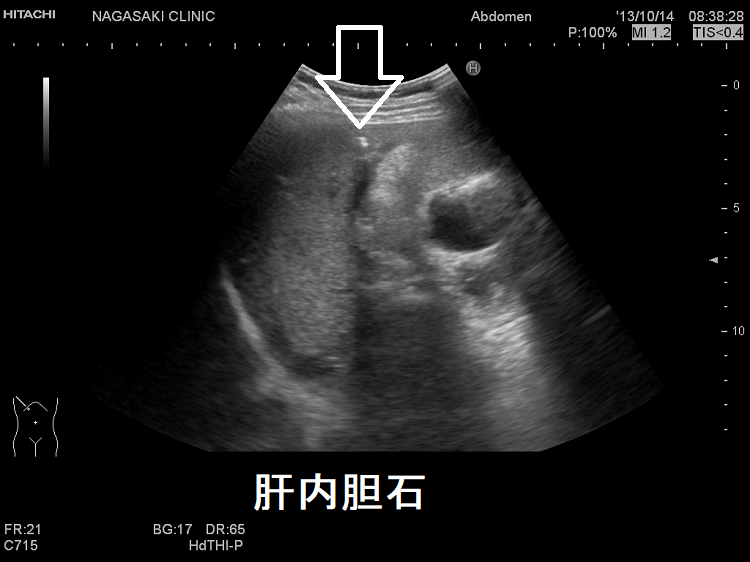

妊娠時一過性尿崩症は妊娠後期に多く、ほぼ全例に肝障害を認め、vasopressinase代謝分解低下が原因の可能性。HELLP症候群(ヘルプ症候群)は①溶血②肝酵素上昇③血小板減少で妊娠高血圧症候群に多く発生。妊娠後期・出産後に突然の心窩部痛・悪心で発症。橋本病など自己免疫抗体保有率が高い。急性妊娠脂肪肝は妊娠後期に発症し超音波エコー検査で診断不能。HELLP症候群(ヘルプ症候群)は、抗甲状腺薬(メルカゾール、プロパジール、チウラジール)肝障害・バセドウ病再発、チラーヂンS錠の肝障害と鑑別。妊娠時の肝内胆汁うっ滞は、甲状腺疾患や糖尿病のリスクを増大。

妊娠時の肝内胆汁うっ滞と、肝臓がん・胆道がんの発生は関連するとの報告があります。特に、C型肝炎や胆石症の妊婦で関連が強いとされます。

さらに、妊娠時の肝内胆汁うっ滞は、甲状腺疾患、乾癬、自己免疫性関節症、クローン病(Crohn 病)、糖尿病のリスクも増加させます。[Clin Res Hepatol Gastroenterol. 2016 Apr;40(2):139-40.]